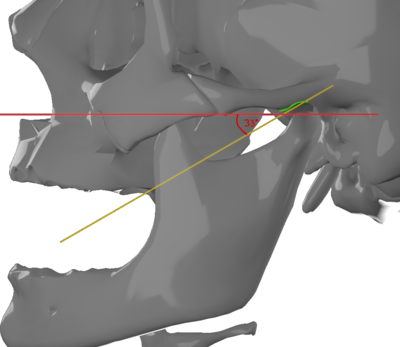

Die Horizontale Kondylenbahnneigung (HCN, Gelenkbahnneigung) ist der Winkel zwischen der Gelenkbahn (tangential anliegende Verbindungslinie zwischen Gelenkgrube und Gelenkhöcker des Kiefergelenks) und der Camperschen Ebene. Sie beträgt mittelwertig 33°. An Mittelwertartikulatoren findet man horizontale Kondylenbahnneigungen von 25° bis 33°.

Die Horizontale Kondylenbahnneigung (HCN, Gelenkbahnneigung) ist der Winkel zwischen der Gelenkbahn (tangential anliegende Verbindungslinie zwischen Gelenkgrube und Gelenkhöcker des Kiefergelenks) und der Camperschen Ebene. Sie beträgt mittelwertig 33°. An Mittelwertartikulatoren findet man horizontale Kondylenbahnneigungen von 25° bis 33°.